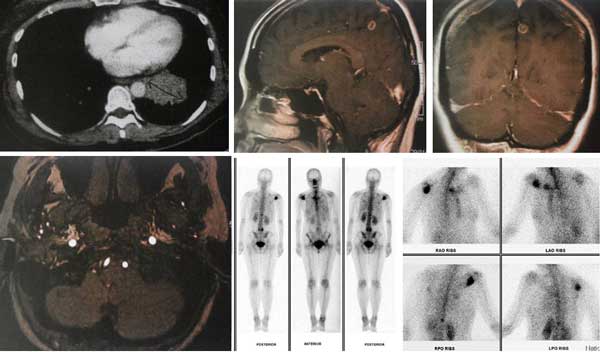

The progress of FY’s treatment was monitored by scanning and blood tests.

CT scan thorax done in Hospital A, 29 August 2017.

- a suspicious 3.4 x 2.8 x 3.3 cm lump in the lower lobe of his left lung.

CT scan of brain, neck, thorax, abdomen and pelvis done in Hospital C, 26 September 2017.

- lesion at apical segment of left lower lobe of lung and small cavities due to primary carcinoma.

- multiple small metastases in both lungs.

- enhancing lesions at left parietal lobe, vermis and right cerebellum.

- patchy sclerosis of body of T1 vertebrae suggestive of metastasis.

- lymph node at level 4 of neck.